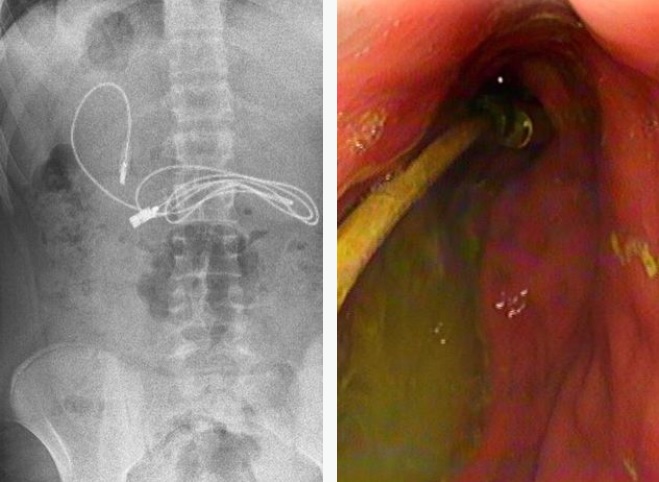

صدم مراهق الأطباء، بعد نقله إلى أحد مستشفيات تركيا وهو يعاني من غثيان شديد وآلام مبرحة في معدته، إذ أظهرت الأشعة المقطعية، ابتلاعه سلك شاحن طوله 90 سنتيمتراً.

وخضع المراهق الذي لم تكشف هويته، إلى عملية عاجلة لاستخراج السلك من معدته، ليتبين أنه ابتلع ربطة شعر، أيضاً، حسب صحيفة ميرور البريطانية.

وقال الطبيب الذي أشرف على الجراحة، إن العملية كانت معقدة لأن أحد طرفي السلك مَر إلى الأمعاء الدقيقة. ولحسن الحظ، تعافى المراهق، 15 عاماً، سريعاً بعد العملية وعاد إلى منزله في ديار بكر بصحة جيدة.